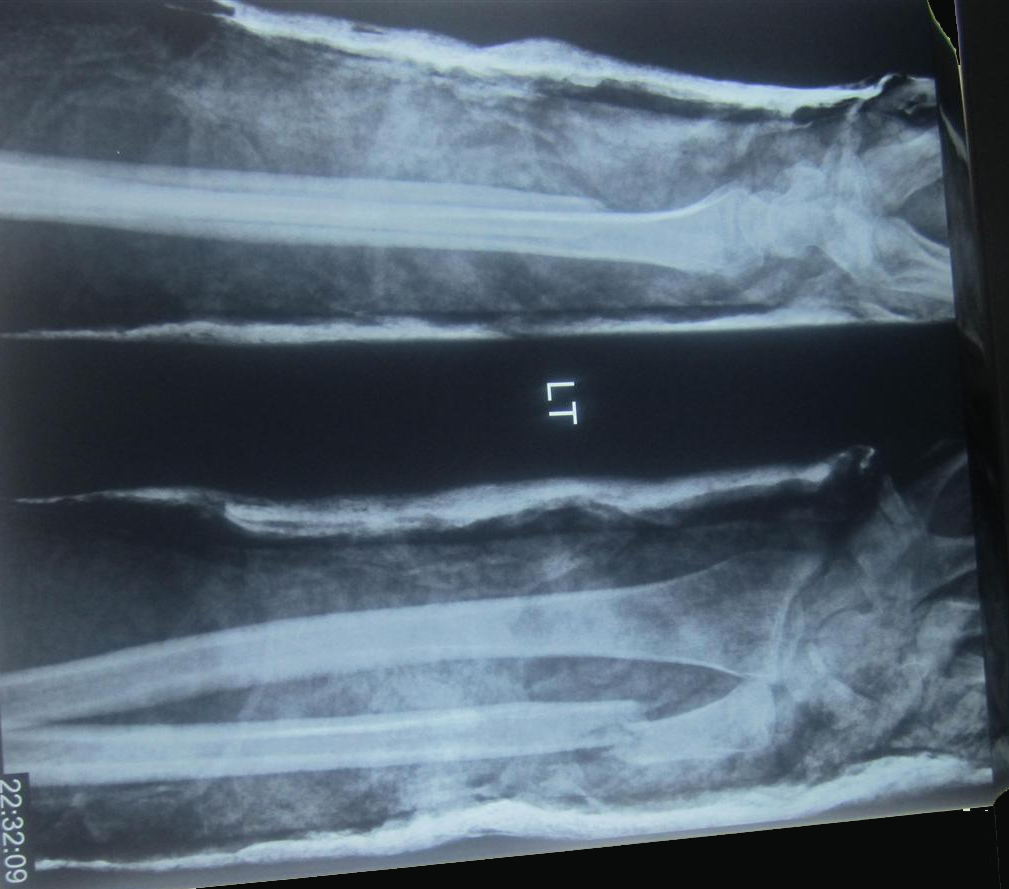

Radius and Ulnar Shaft Fractures Trauma Orthobullets Radius Ulna Fracture Orthobullets distal radius fractures are the most common upper extremity fracture and account for over a sixth of all fractures seen in emergency. — distal radius fractures are the most common orthopaedic injury and generally result from fall on an outstretched hand. — radius and ulnar shaft fractures, also known as adult both bone forearm fractures, are common. Radius Ulna Fracture Orthobullets.

Radius and Ulnar Shaft Fractures Trauma Orthobullets Radius Ulna Fracture Orthobullets — radius and ulnar shaft fractures, also known as adult both bone forearm fractures, are common fractures. distal radius fractures are the most common upper extremity fracture and account for over a sixth of all fractures seen in emergency. — distal radius fractures are the most common orthopaedic injury and generally result from fall on an outstretched. Radius Ulna Fracture Orthobullets.